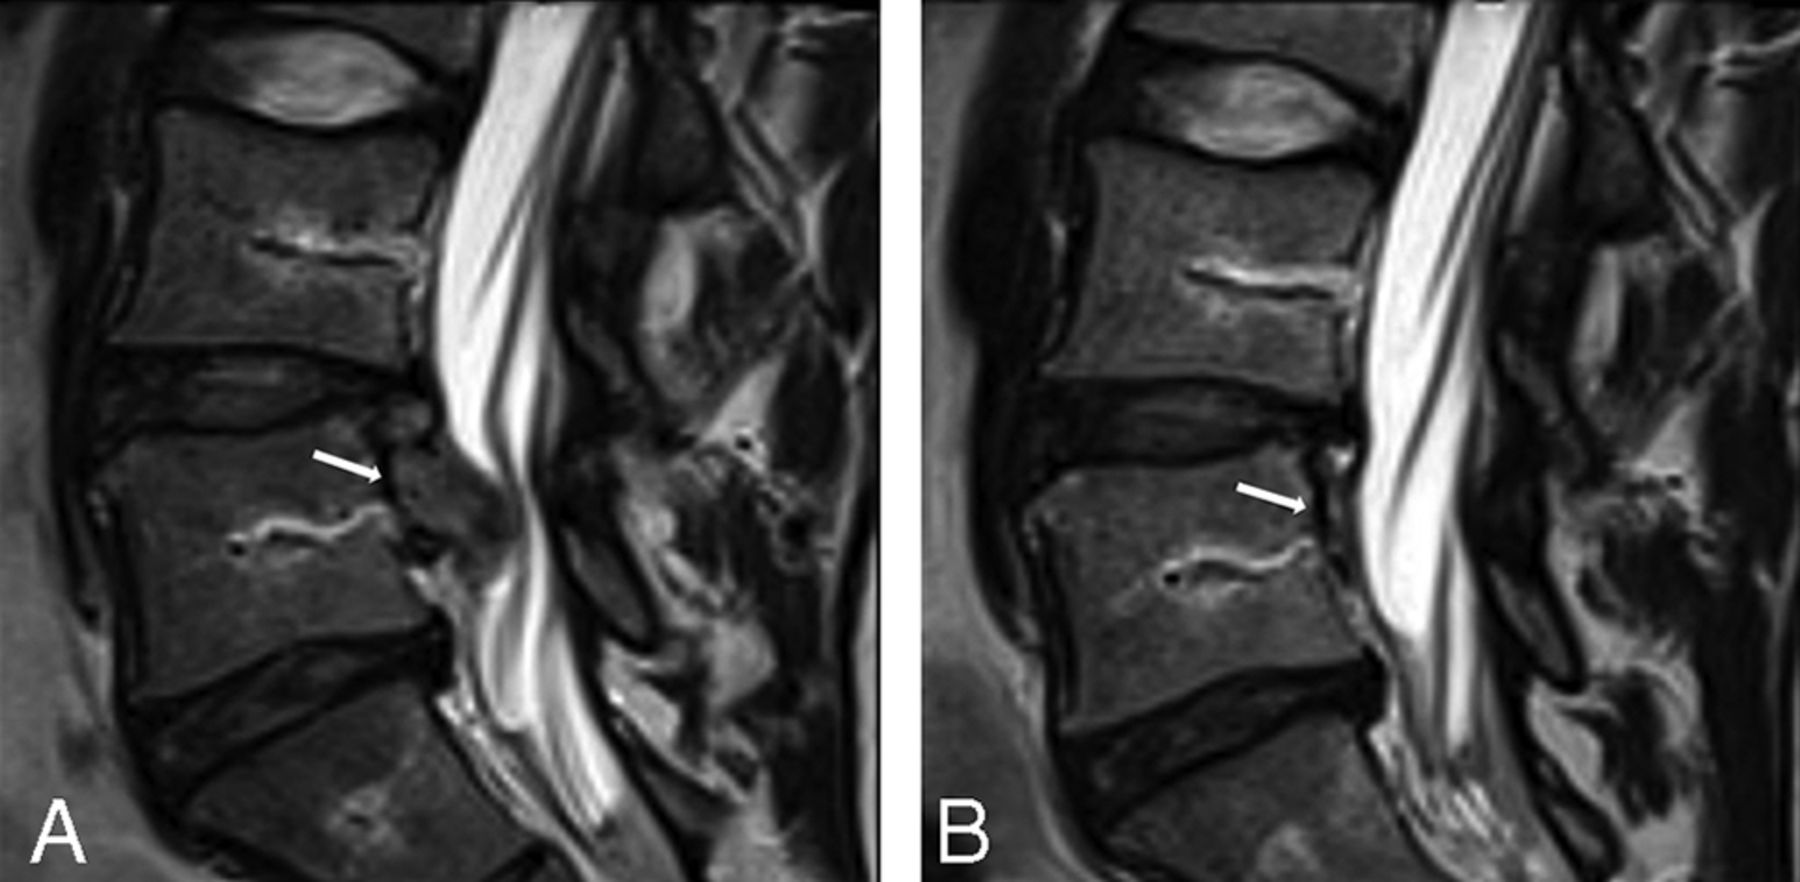

Images of a high-intensity zone from 1 participant with LBP showing evidence of probable change.